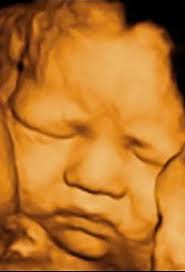

When Is It The Best Time To Do A 3d 4d Ultrasound December 2018 Babies Forums What To Expect

When Is It The Best Time To Do A 3d 4d Ultrasound December 2018 Babies Forums What To Expect from images.agoramedia.com